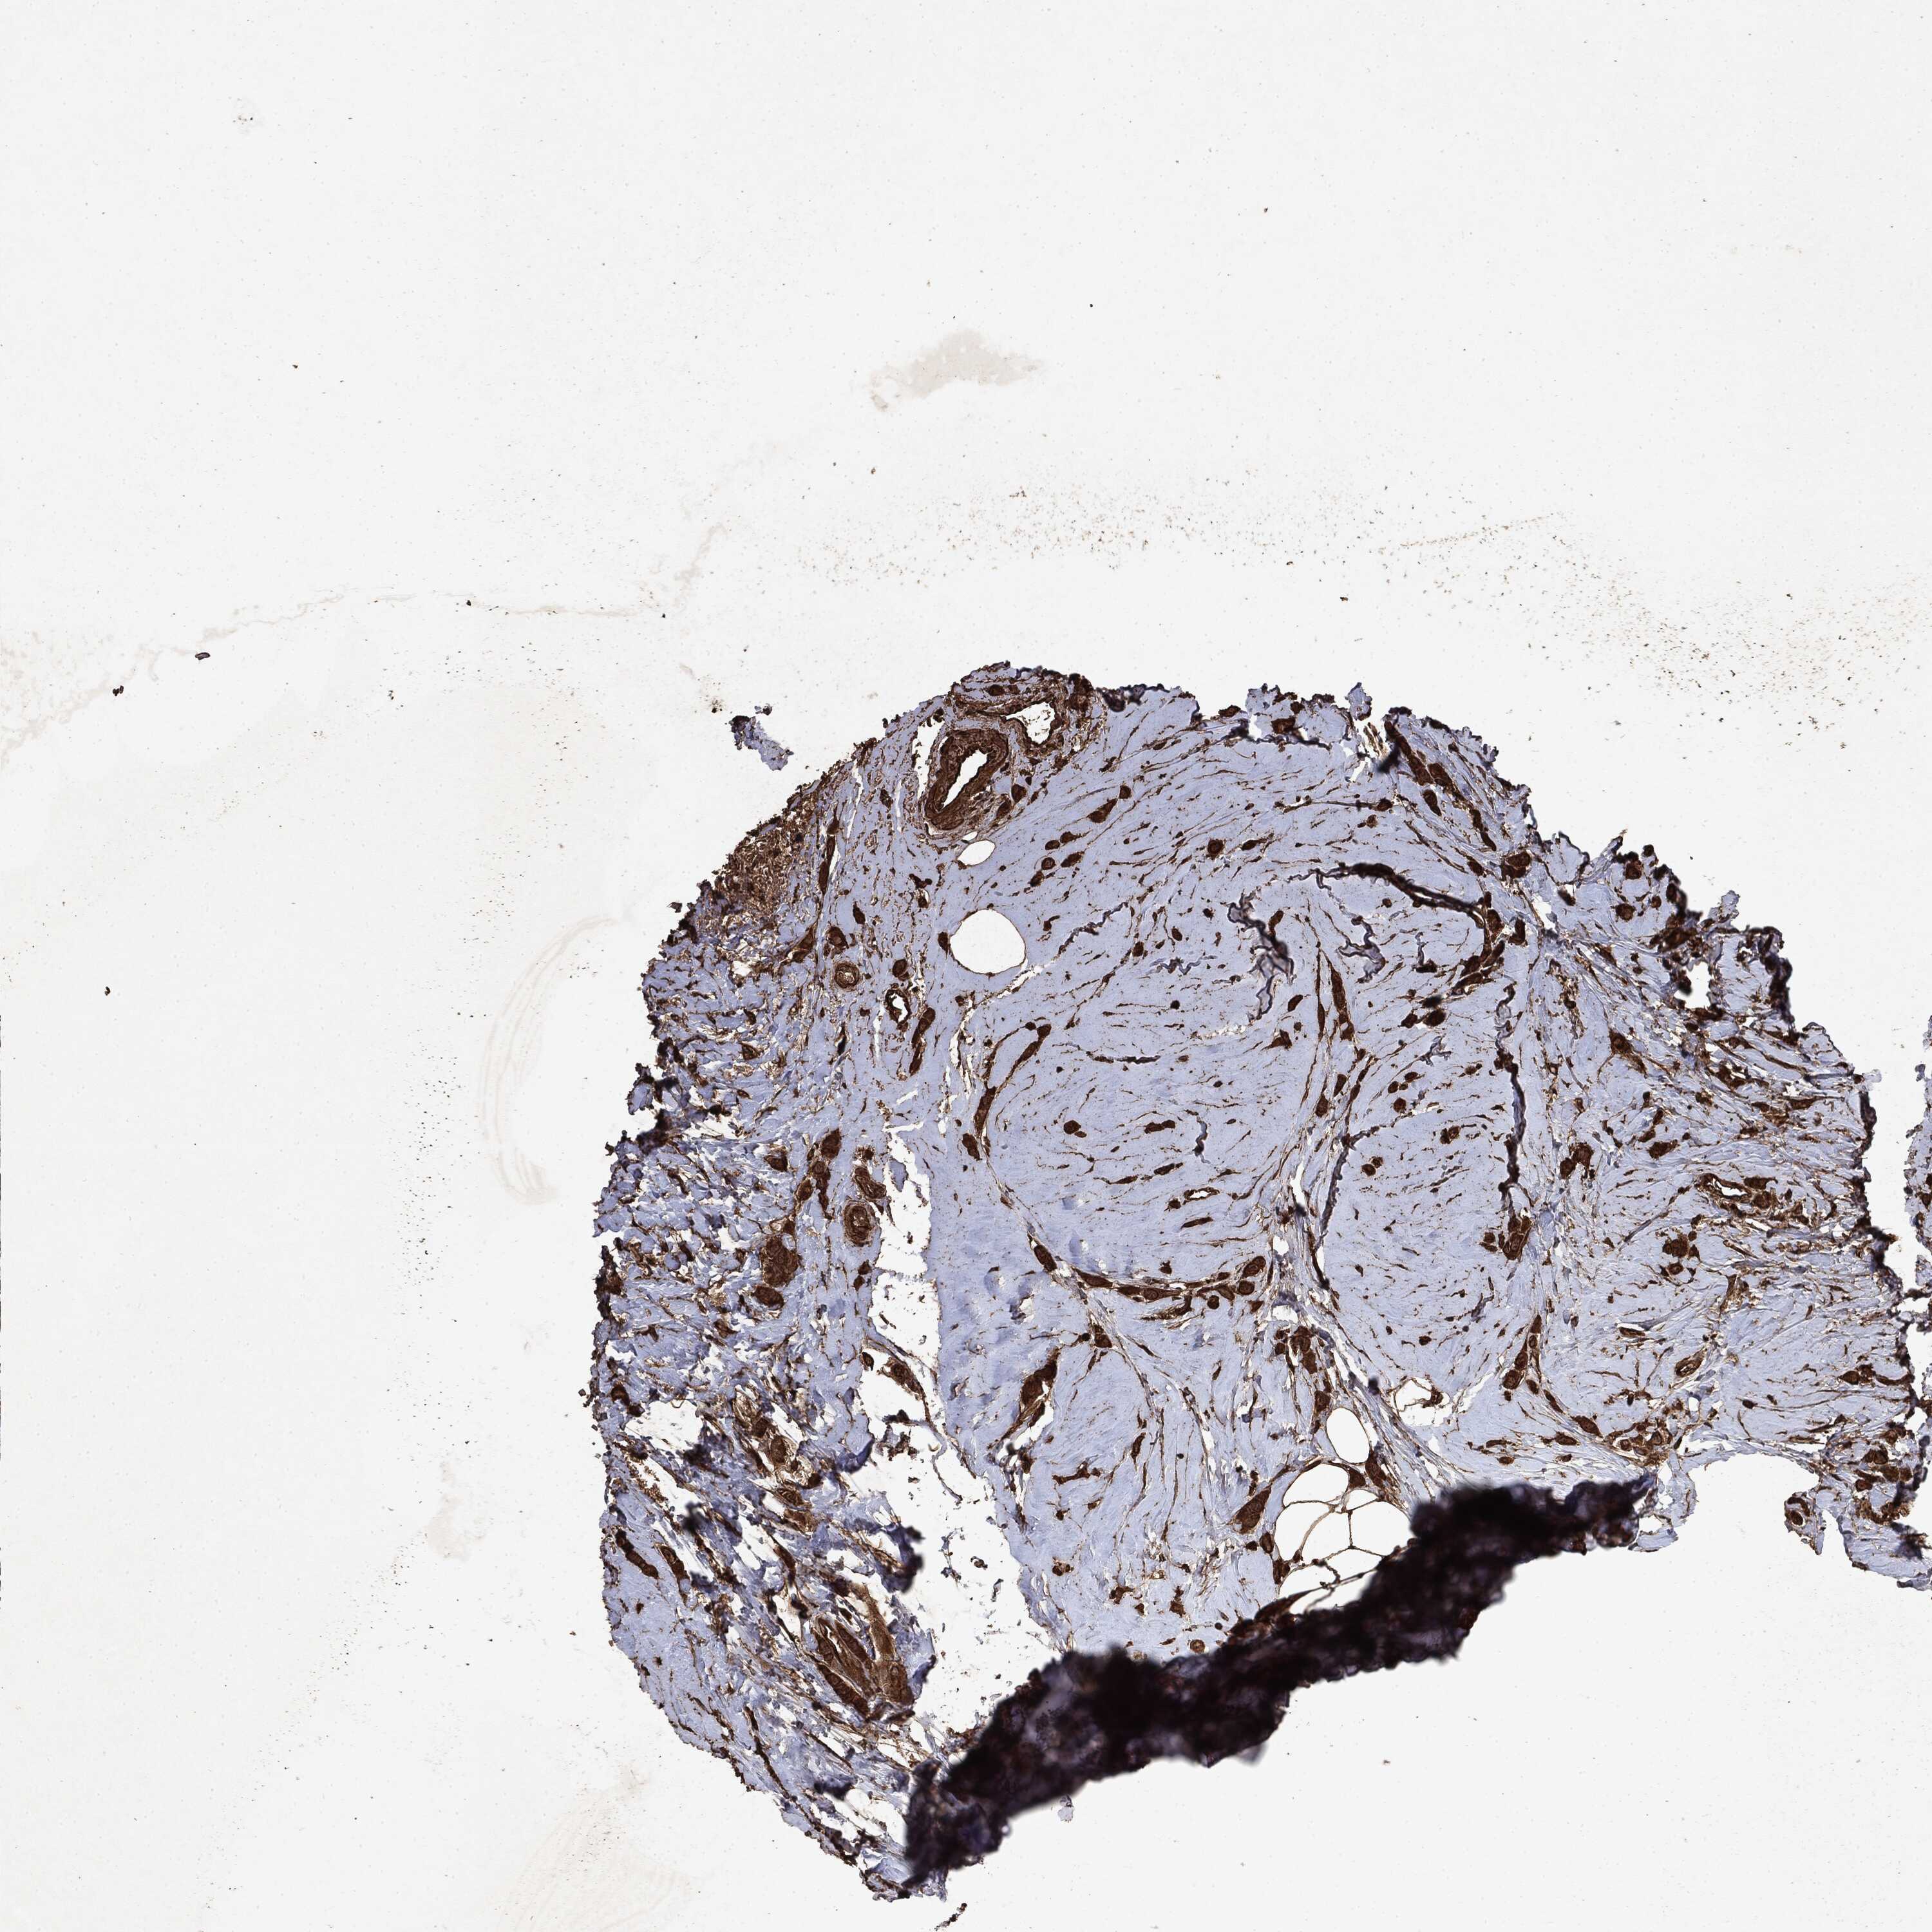

BRCA TCGA BRCA VALIDATION PROTEIN EXPRESSION

ANTIBODIES

AND

VALIDATION